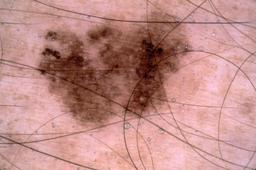

{

"age_approx": 45,

"anatom_site_general": "anterior torso",

"concomitant_biopsy": true,

"dermoscopic_type": "contact non-polarized",

"diagnosis_1": "Malignant",

"diagnosis_2": "Malignant melanocytic proliferations (Melanoma)",

"diagnosis_3": "Melanoma, NOS",

"diagnosis_confirm_type": "histopathology",

"image_type": "dermoscopic",

"lesion_id": "IL_3573306",

"melanocytic": true,

"patient_id": "IP_7383530",

"sex": "male"

}